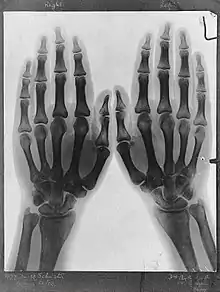

Radiograph of hands by Arthur Schuster